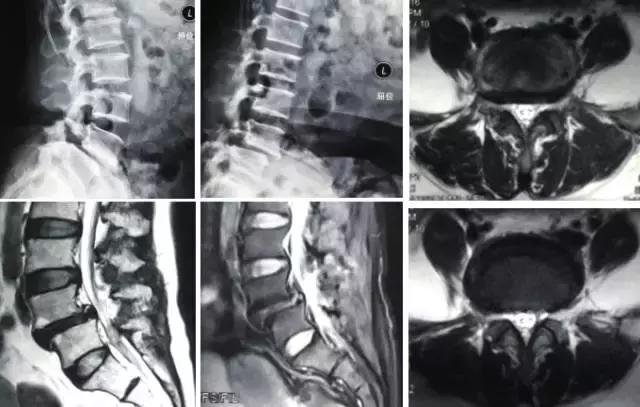

▲手术后X线平片

▲手术后MRI